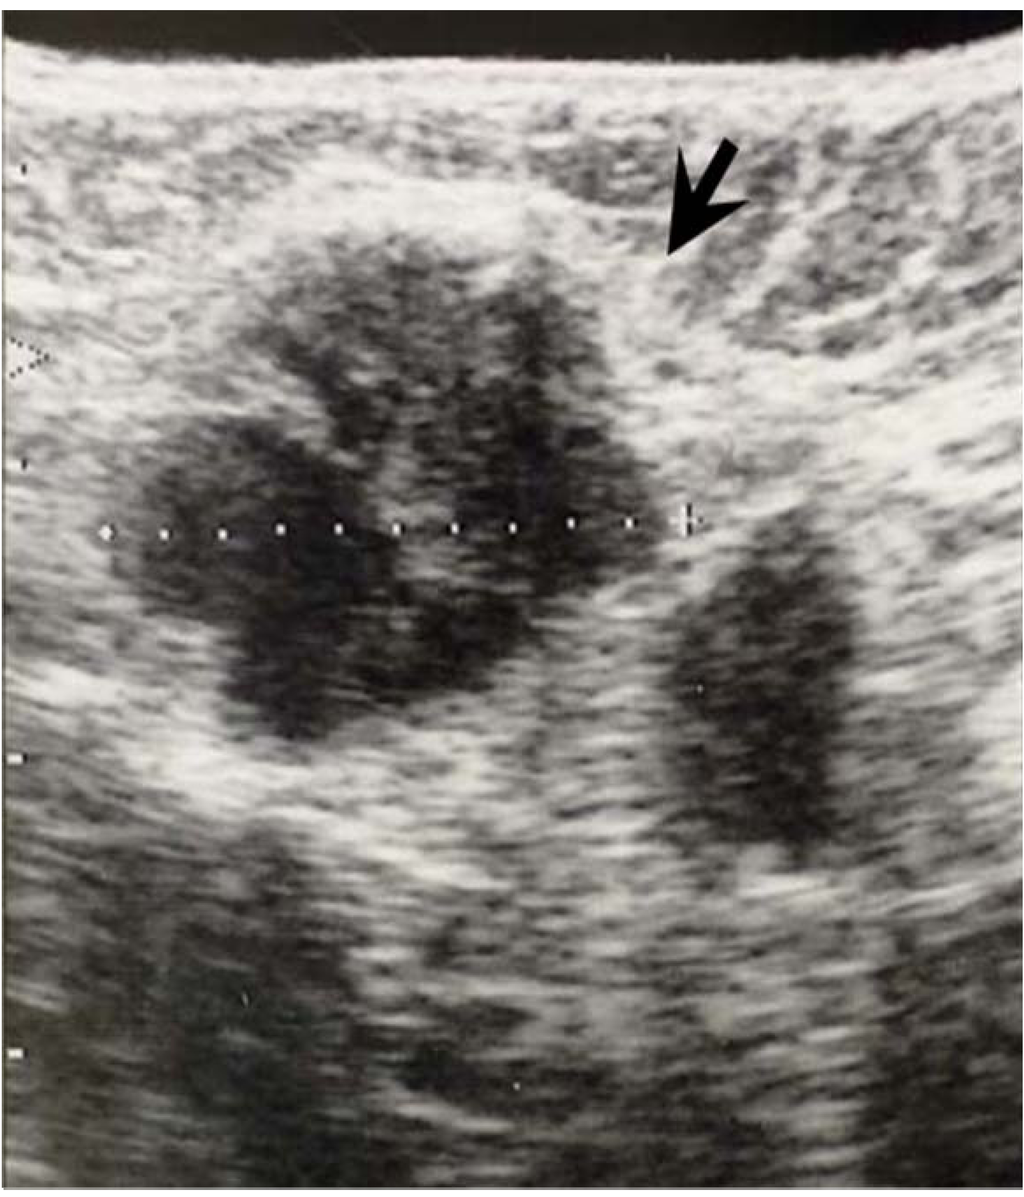

3.2. Ultrasonographic Examination and Criteria for Axillary node Evaluation